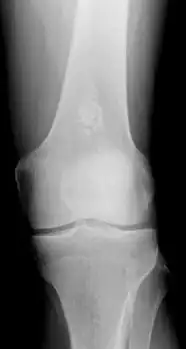

Diagnosistic tests include medical imaging.[2] Appearances on X-ray show a small lobe-shaped, dark tumor in the middle of the bone.[2] It typically contains white spots; calcified chondroid matrix (a "rings and arcs" pattern of calcification).[2] It does not extend into soft tissues.[6] Magnetic resonance imaging (MRI) and CT scan may be requested to further evaluate the tumor.[8]

X-ray: Solitary enchondroma in long bone of thigh near knee

Differentiating an enchondroma from a bone infarct on plain film may be difficult. Generally, an enchondroma commonly causes endosteal scalloping while an infarct will not. An infarct usually has a well-defined, sclerotic serpentine border, while an enchondroma will not. When differentiating an enchondroma from a chondrosarcoma, the radiographic image may be equivocal; however, periostitis is not usually seen with an uncomplicated enchondroma.